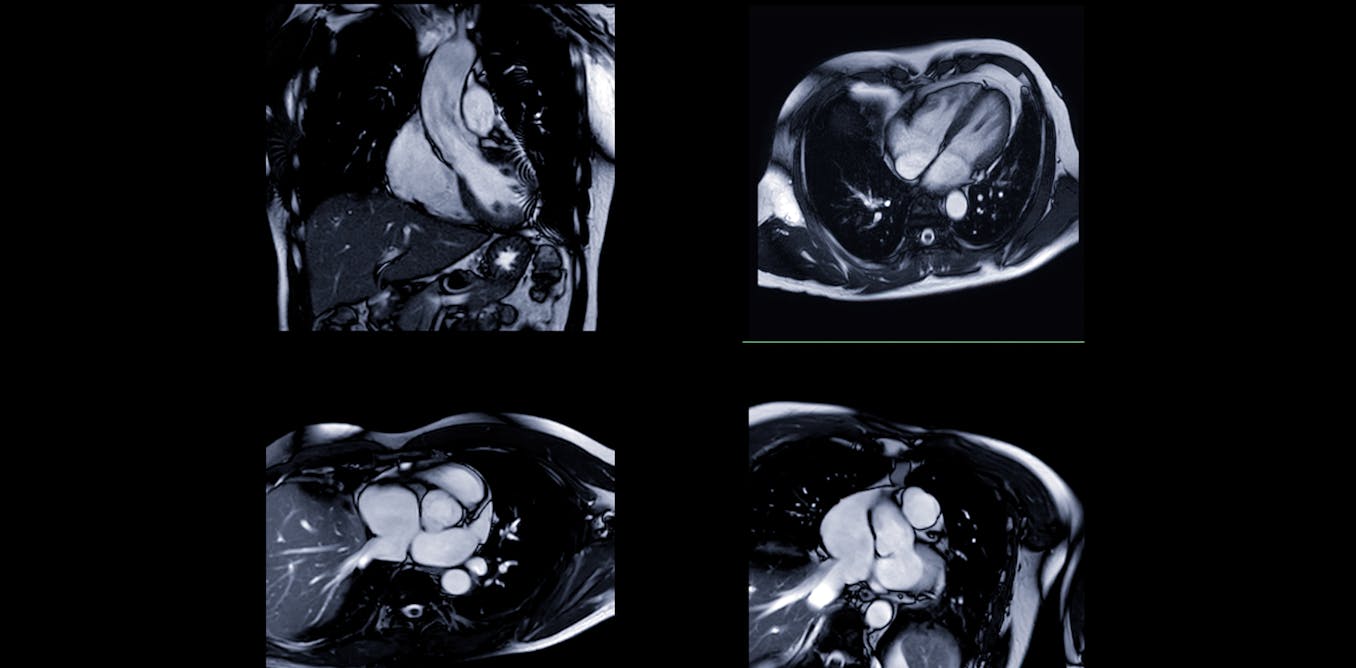

My recent study, which I conducted with colleagues, found that an AI model could guess whether a patient identified as Black or white from heart images with up to 96% accuracy – despite no explicit information about racial categories being given.

AI systems are already transforming healthcare. They can analyse chest X-rays, read heart scans and flag potential issues faster than human doctors – in some cases, in seconds rather than minutes. Hospitals are adopting these tools to improve efficiency, reduce costs and standardise care.

In the heart scan study, researchers found that the AI model wasn’t actually focusing on the heart itself, where there were few visible differences linked to racial categories. Instead, it drew information from areas outside the heart, such as subcutaneous fat as well as image artefacts – unwanted distortions like motion blur, noise, or compression that can degrade image quality. These artefacts often come from the scanner and can influence how the AI interprets the scan.

In this study, Black participants had a higher-than-average BMI, which could mean they had more subcutaneous fat, though this wasn’t directly investigated. Some research has shown that Black individuals tend to have less visceral fat and smaller waist circumference at a given BMI, but more subcutaneous fat. This suggests the AI may have been picking up on these indirect racial signals, rather than anything relevant to the heart itself.

Build transparency: many AI systems are considered “black boxes” because we don’t understand how they reach their conclusions. The heart scan study used heat maps to show which parts of an image influenced the AI’s decision, creating a form of explainable AI that helps doctors and patients trust (or question) results – so we can catch when it’s using inappropriate shortcuts.